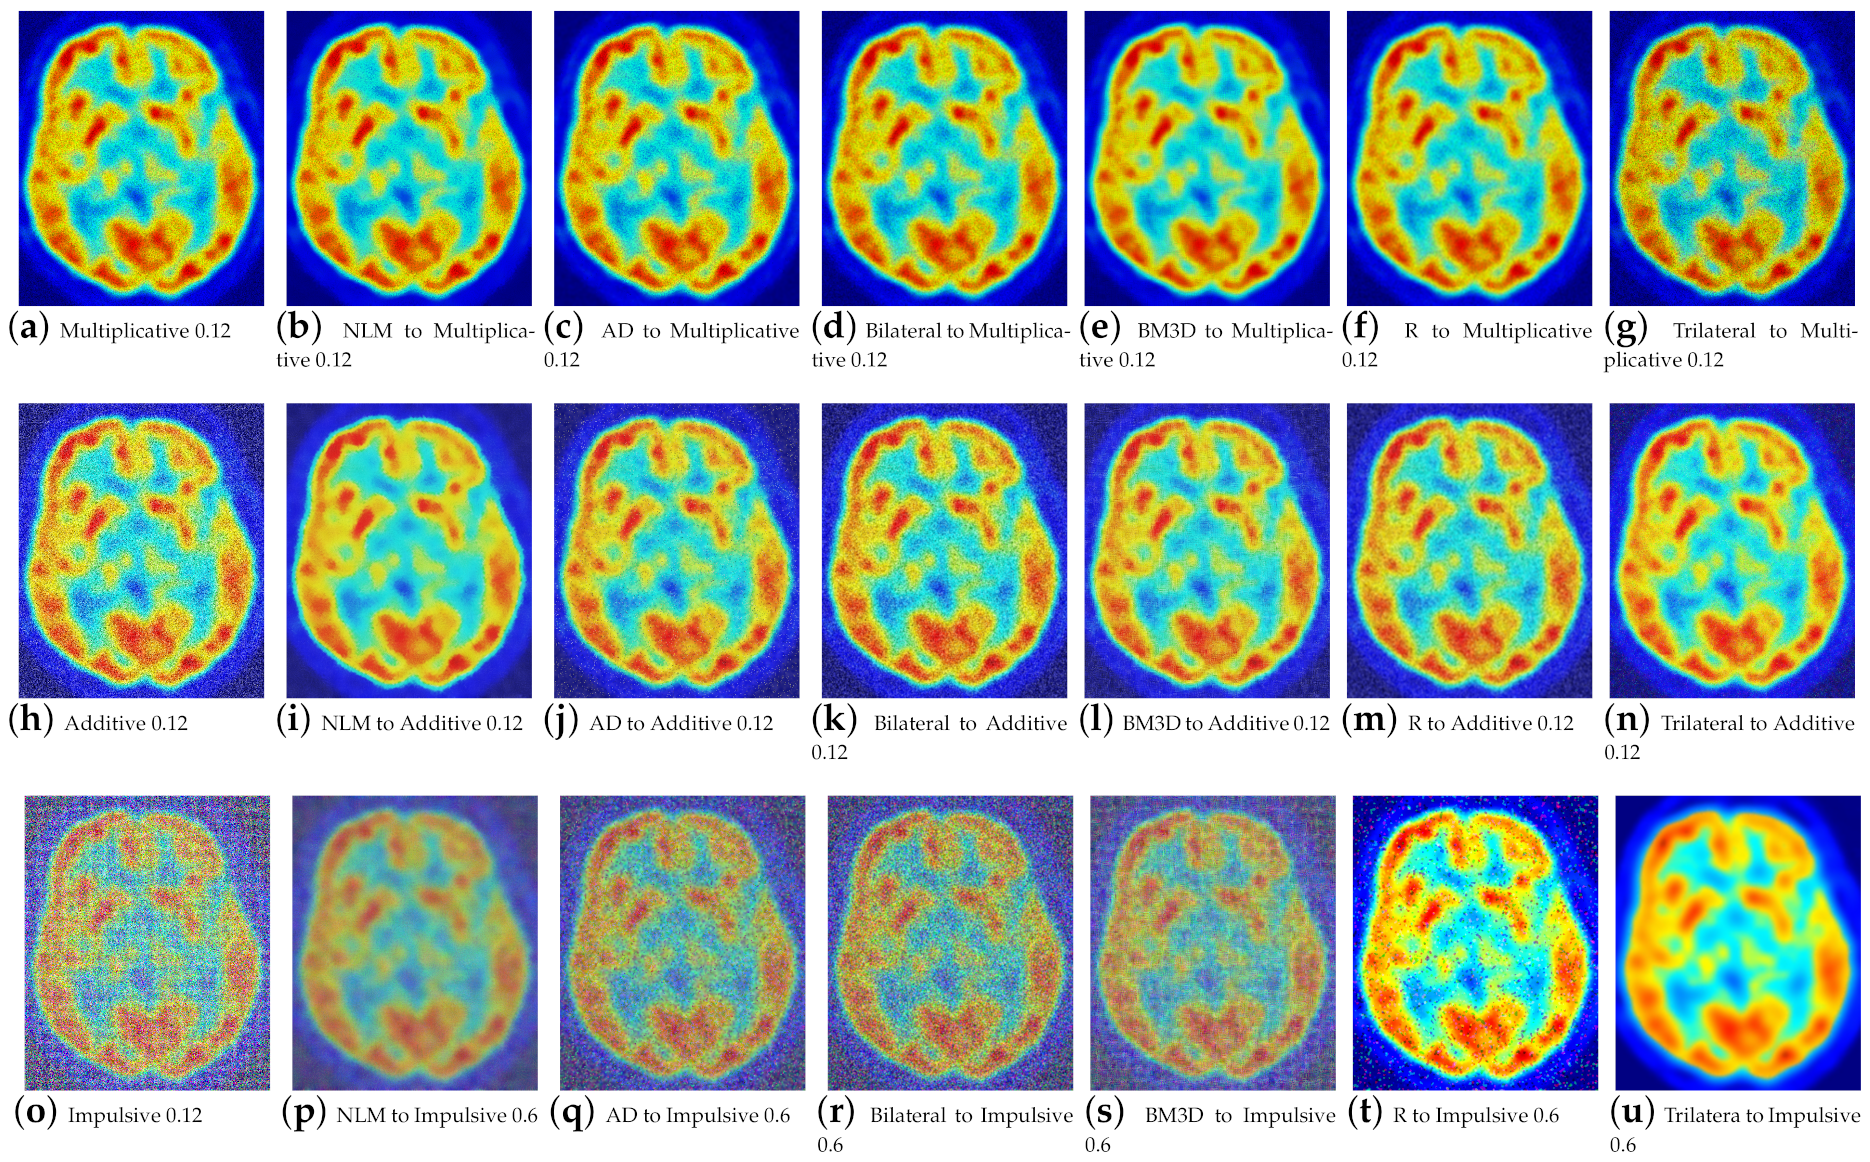

Figure 4 confirms that the filtered Lena image using redescending functions aligns with the expected metric results. Improved performance is observed at high noise densities for both additive and multiplicative noise with the Insha estimator, while visually, the processed images exhibit better preservation of details. In contrast, the Hampel estimator shows superior results for impulsive noise at low densities.

Figure 4.

Qualitative results of the redescending (R), NLM, AD, BM3D, and bilateral Lena image.

Figure 5 presents the results for images e2, e3, and e4, demonstrating the effectiveness of the proposed filter in efficiently removing various types of noise from medical images.

Figure 5.

Results of redescending (R), NLM, and AD for the existing and proposed methods at low noise densities (additive = 0.02, multiplicative = 0.02, and impulsive = 0.1) and high noise densities (additive = 0.12, multiplicative = 0.12, and impulsive = 0.6).

The fact that three channels of information are now being processed has resulted in an increase in information, which in turn has led to improved performance for the proposed work. For high-density noise experimentation, the standard color images, i.e., Lena, Baboon, Goldhill, Boats, Barbara, and Peppers, were used, along with a positron emission tomography (PET) image. Quantitative results for color image filtering can be seen in Figure 6 for the baboon image and in Figure 7 for brain PET. One can observe how the increase in information benefits the proposed filter, especially for impulsive noise.

Figure 7.

Results of filtering of the brain PET image at high densities.